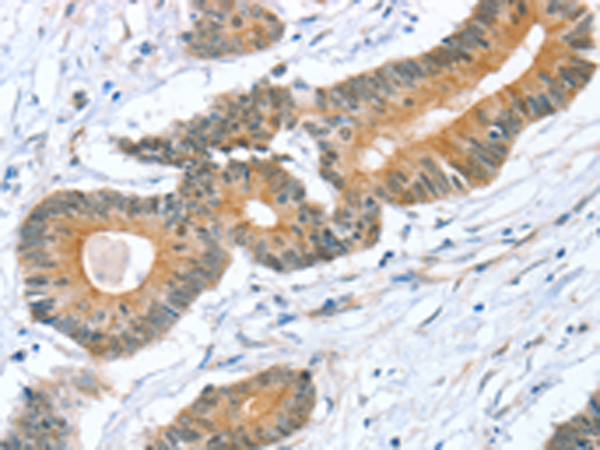

分类: 科研抗体货号: P08819别名: ST1B1; ST1B2; SULT1B2应用: WB,IHC反应种属: Human